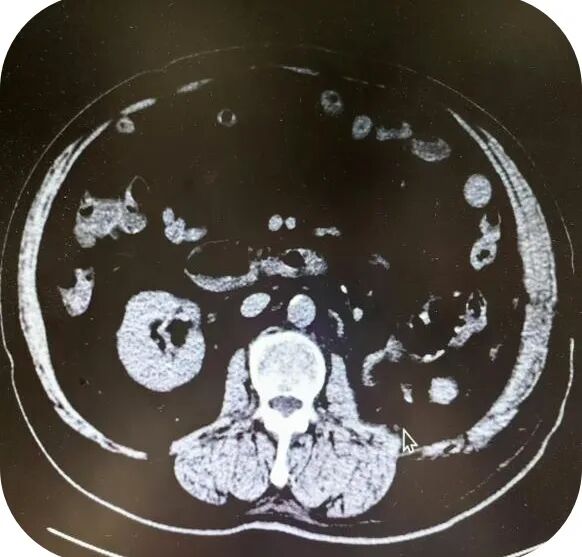

近日,贵州航天医院泌尿外科团队成功为一名患者实施了全腹腔镜下巨大肾癌根治术,这不仅标志着泌尿外科团队医疗技术的一次重大突破,更为患者在家门口带来了治疗的希望。 案例分享 67岁的王先生因“体检发现左肾包块1年”,发现时未予重视及治疗,但近期发现腹部包块增大就前往我院泌尿外科门诊就诊。患者入院后检查发现肌酐轻度升高,泌尿系增强CT及MRI均强烈提示左肾存在恶性肿瘤性病变,包块大小约200×150×120mm,且右侧骼骨高密度影提示需排除骨转移可能。 在与患者及家属沟通后,他们坚持手术治疗,泌尿外科主任石英、副主任医师李凯多次组织相关医生进行术前讨论和评估,精准设计手术方案,在泌尿外科团队奋战2小时后,成功为患者实施全腹腔镜下巨大肾癌根治术,切除巨大肾脏肿瘤。术后病理确诊为肾细胞癌,左侧肾上腺皮质有增生伴多发小结节,周围组织未见癌浸润。患者术后恢复良好,1周后便安全出院。 术 前 术 后 1 什么是肾癌 肾癌,全称为肾细胞癌,是指肾脏细胞发生癌变,异常地生长、增殖并向其他全身器官侵袭、转移的一种恶性疾病。它是原发于肾细胞的一种癌症,有多种细胞类型,其中60%~85%为透明细胞癌,主要源于肾小管上皮细胞。肾癌的瘤体多为实性,表现为类圆形肿块。 2 肾癌的症状 早期: 肾癌早期通常没有典型的症状,多数患者是在体检或做B超、CT检查时发现肾脏有占位性病变。 中晚期: 1.腰痛、腹部包块或肉眼血尿。 2.由于肾癌吸收大量的血红素和营养成分,导致肾脏促红素分泌下降,出现贫血现象。 3.少数肾癌病人会出现病理性转移,引起病理性骨折现象。 4.肾癌病人还可能出现泌乳现象。 5.由于肿瘤局部转移或局部扩散,肾癌病人还可能出现局部疼痛和肠梗阻症状,部分病人还会出现消瘦、恶液质现象。 6.当肾癌引起肾脏静脉瘤栓并导致下腔静脉梗阻时,还会出现下肢水肿症状。 3 全腹腔镜下巨大肾癌根治术如何治疗肾癌? 全腹腔镜下巨大肾癌根治术是一种比较先进的手术方式,它利用腹腔镜技术,通过微小切口在腹腔或后腹膜腔途径进行手术,完整切除整个肾脏及其周围可能受累的组织。 手术过程中,医生会在患者腹部做几个小切口,通过这些切口插入腹腔镜及其相关手术器械。腹腔镜具有高清摄像功能,能够将腹腔内的图像实时传输到显示器上,使医生能够清晰地看到手术部位。在腹腔镜的引导下,医生进行精确的手术操作,切除整个肾脏及其周围筋膜内的组织。 4 全腹腔镜下巨大肾癌根治术优势 与传统的开放手术相比,全腹腔镜下巨大肾癌根治术具有以下优点: 创伤小:手术切口小,减少了组织损伤和出血量。 恢复快:术后患者疼痛轻,恢复速度快,缩短了住院时间。 并发症少:由于手术操作精确,减少了术后并发症的发生。 美观性好:手术切口小且隐蔽,有利于保持患者的美观性。 注:图片来源于网络,如有侵权,请联系删除。 推荐 阅读 1.【航医精品】泌尿外科精品技术介绍——经尿道钬激光前列腺剜除术(HoLEP) 贵州航天医院泌尿外科 专家团队 石 英 泌尿外科主 任 学科带头人 主任医师 中国医师协会泌尿外科分会感染协作组委员,奥林巴斯泌尿系软镜西南区专家组成员,西南地区第一批输尿管软镜专家组成员,贵州省医学会泌尿外科分会委员,贵州省性学会理事,贵州省性学会常务委员,贵州省泌尿外科专业医疗质量控制中心专家委员会委员。 从事泌尿外科专业近30年,熟练掌握泌尿系各类疾病的诊治,具有丰富的临床经验,擅长泌尿系结石、腹膜后肿瘤及泌尿系肿瘤的手术治疗,对泌尿系感染、泌尿系结核、尿源性脓毒血症的救治有独到的见解及抢救经验,在贵州省率先引入输尿管软镜技术,同时在男科领域,对男性阳痿、早泄及前列腺疾病有很深的研究。 李 凯 泌 尿 外 科 副 主 任 医 师 贵州航天医院肿瘤腔镜组带头人,擅长肾癌根治术、输尿管癌根治术、膀胱及前列腺癌根治术、腹腔镜输尿管狭窄切除吻合术、输尿管切开取石术等手术,在遵义市率先开展泌尿系结核后膀胱挛缩全腹腔镜下膀胱扩大术。 贵州省医学会泌尿外科分会青年委员,遵义市医学会男科分会常务委员,遵义市医学会泌尿外科分会常务委员。 李国成 泌 尿 外 科 副 主 任 医 师 中国人体健康科技促进会男科学专业委员会委员,贵州省性学会泌尿外科分会委员,贵州省医学会男科学分会委员,遵义市医学会男科学分会副主任委员兼秘书长,遵义市医学会泌尿外科分会常务委员,贵州航天医院男科带头人。 从事泌尿外科及男科工作10余年,曾多次在上海交通大学附属第一人民医院,中国中医科学院西苑医院进修学习男科;擅长性功能障碍的诊治,男性整形手术,前列腺增生激光手术,显微手术等。 贵州航天医院泌尿外科简介 • ✦ 基本情况 ✦ • 贵州航天医院泌尿外科是贵州省临床重点专科,具备先进检查及治疗设施,可进行各种泌尿外科所需临床检查和治疗。拥有先进的美国科医人钬激光碎石及前列腺剜除系统、体外冲击波碎石机、等离子电切设备、奥林巴斯输尿管软镜、STORZ输尿管电子软镜、腹腔镜、膀胱镜、输尿管镜、肾镜、美国KLS能量平台及各种显示系统,男科专用的ED超声治疗仪、精液分析、显微镜、男科检查平台、尿动力仪、结石分析仪等。 除了传统的开放性手术外,已常规开展各种微创性手术,同时在尿动力学及结石成分方面的研究已走在省内前列,在贵州省内率先开展前列腺钬激光剜除术治疗前列腺增生症,等离子电切术在前列腺增生、膀胱肿瘤、在尿道狭窄中手术的应用,腹腔镜手术(肾囊肿、肾上腺肿瘤、肾输尿管结石及肾切除手术),肾癌、肾盂癌、输尿管癌、膀胱癌、前列腺癌根治术,泌尿系统畸形及泌尿系重建,在遵义地区率先开展钬激光技术应用于泌尿外科临床,率先使用输尿管硬镜、软镜及肾镜联合钬激光治疗泌尿系结石,开展尿动力学、泌尿系结石分析,填补了遵义地区空白,率先开展针状肾镜激光碎石取石术。 • ✦ 诊疗范围 ✦ • 一、泌尿系肿瘤、炎症、小儿泌尿系疾病、男科疾病、女性排尿异常与盆底功能障碍疾病。如:肾上腺肿瘤、肾肿瘤、肾盂输尿管肿瘤、膀胱肿瘤、前列腺肿瘤、生殖器肿瘤、排尿功能障碍、泌尿系畸形及肾后性肾功能障碍、女性尿道综合征、泌尿系感染以及泌尿道疼痛、婴幼儿男性性腺和性器官发育异常、青春期男性性器官和功能发育延迟、男性生殖功能障碍、男子节育与避孕、中老年男子生殖健康以及老年男子性腺功能减退症、生殖器官常见疾病、男性生殖器感染以及性传播疾病、外生殖器官畸形与矫形、损伤。 二、泌尿系结石。如:肾结石、输尿管结石、膀胱结石、前列腺尿道结石、泌尿系畸形合并结石、尿流改道术后合并泌尿系结石。 三、独立开展男科疾病诊治,设有单独男科门诊。 • ✦ 咨询信息 ✦ • 门 诊 地 址:门诊部110诊室 坐诊时间: 周一至周五(08:00-12:00;13:00-17:00) 周末及节假日(08:00-12:00;13:00-16:00) 咨询电话 门 诊:28690349 医生办公室:27677326 病房护士站:27677518 END